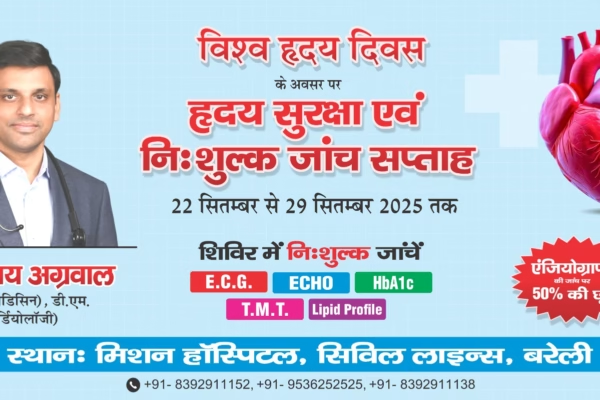

Mission Hospital’s 7-Day Free Health Camp on the Occasion of World Heart Day

Mission Hospital, Bareilly has announced the launch of a seven-day free health camp on the occasion of World Heart Day,…

Mission Hospital, Bareilly has announced the launch of a seven-day free health camp on the occasion of World Heart Day,…